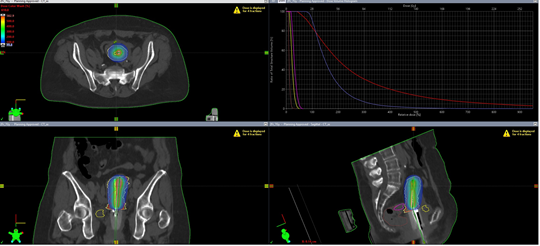

Процедура начинается еще до самого сеанса облучения: на этапе планирования используется магнитно-резонансный томограф, который с высокой точностью определяет не только границы опухоли, но и расположение критически важных органов — мочевого пузыря и прямой кишки. Благодаря этим данным и особой конструкции аппликатора Rotte Y, источник излучения (Иридий-192) доставляется точно в заданную зону.

Конструкция аппликатора работает как интеллектуальный щит: она позволяет сконцентрировать высокоэнергетическую дозу строго в очаге поражения, сводя к минимуму лучевую нагрузку на здоровые ткани. Результат такого подхода — не просто эффективное разрушение опухоли, а принципиально иное качество жизни после лечения, с минимальными побочными эффектами.